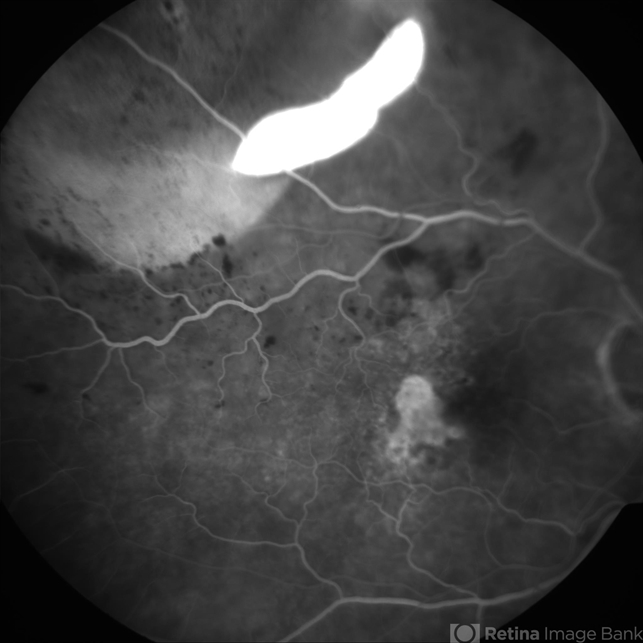

- Spontaneous RPE rip in NV AMD

- pigment epithelial detachment (PED), retinal pigment epithelium (RPE) tear

- 80-year-old female with subfoveal occult CNV and large extrafoveal PED which underwent spontaneous RPE rip. FA shows intense hyperfluorescence in area of absent RPE, progressive filling of extrafoveal PED, and hyperfluorescence in macula from atrophy and occult CNV.